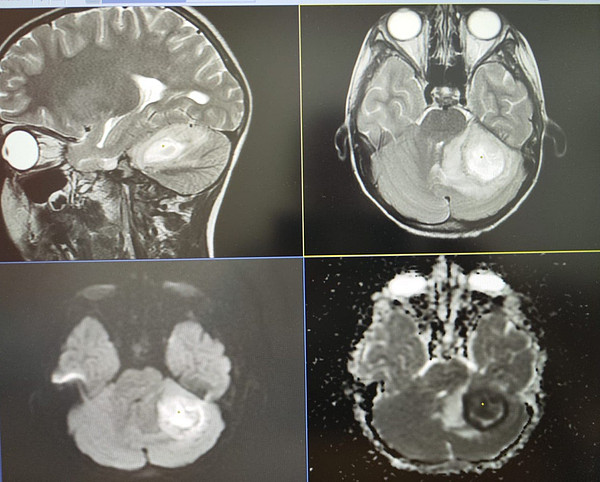

IMG_20240806_161312.